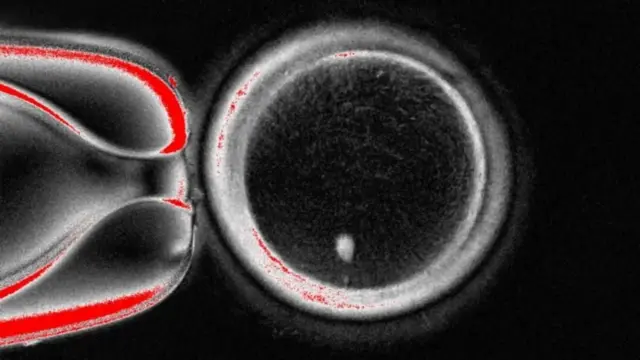

ተመራመርቲ ኣመሪካ፡ ንፈለማ እዋን ካብ ዋህዮ ቈርበት ዝተወስደ ዲኤንኤ ተጠቒሞም፡ ምስ ዘርኢ ወዲ ተባዕታይ ብምድቓል ድቂ ከም ዝፈጠሩ ገሊጾም።

ኣባላት ጕጅለ ምርምር ጥዕናን ሳይንስን ዩኒቨርሲቲ ኦሪገን፡ ሰብነት ንምህናጽ ዘድልዩ ቅድሓት ጀኔቲክ ኮድ ዝሓዘ ኒዩክለስ ካብ ህዋሳት ቈርበት ወሲዶም።

እዚ ድማ፡ ኣብ ውሽጢ ካብ ለጋሲት ዝተረኽበ እንቋቝሖ ክቕመጥ ይግበር።

ብ1996 (ኣ.ኤ)፡ ንፈለማ እዋን 'ዶሊ' ዝተባህለ በጊዕ ንምፍጣር ኣብ ረብሓ ዝወዓለ ክሎኒንግ ዝተባህለ ቴክኒክ ግብራዊ ብምግባር እዩ ተሰሪሑ ነይሩ።

እንተዀነ፡ እዚ እንቋቝሖ ሙሉእ ክሮሞዞም ስለ ዘለዎ፡ በቲ ዘርኢ ወዲ ተባዕታይ ንክራባሕ ድልዊ ኣይኸዉንን።

ኔቸር ኮሚዩኒኬሽን ዝተባህለ መጽሄት ኣብ ዘሕተሞ መጽናዕቲ፡ 82 ድሉዋት ዝዀኑ እንቋቍሖ ከም ዝተሰርሑ የርኢ።

እዚኦም፡ ምስ ዘርኢ ወዲ ተባዕታይ ዝተራኸቡ ኰይኖም፡ ገሊኦም ናብ ደረጃ ድቂ በጺሖም ኣለው። ንልዕሊ ሽዱሽተ መዓልቲ ግን ከይተዳለው እዮም ጸኒሖም።